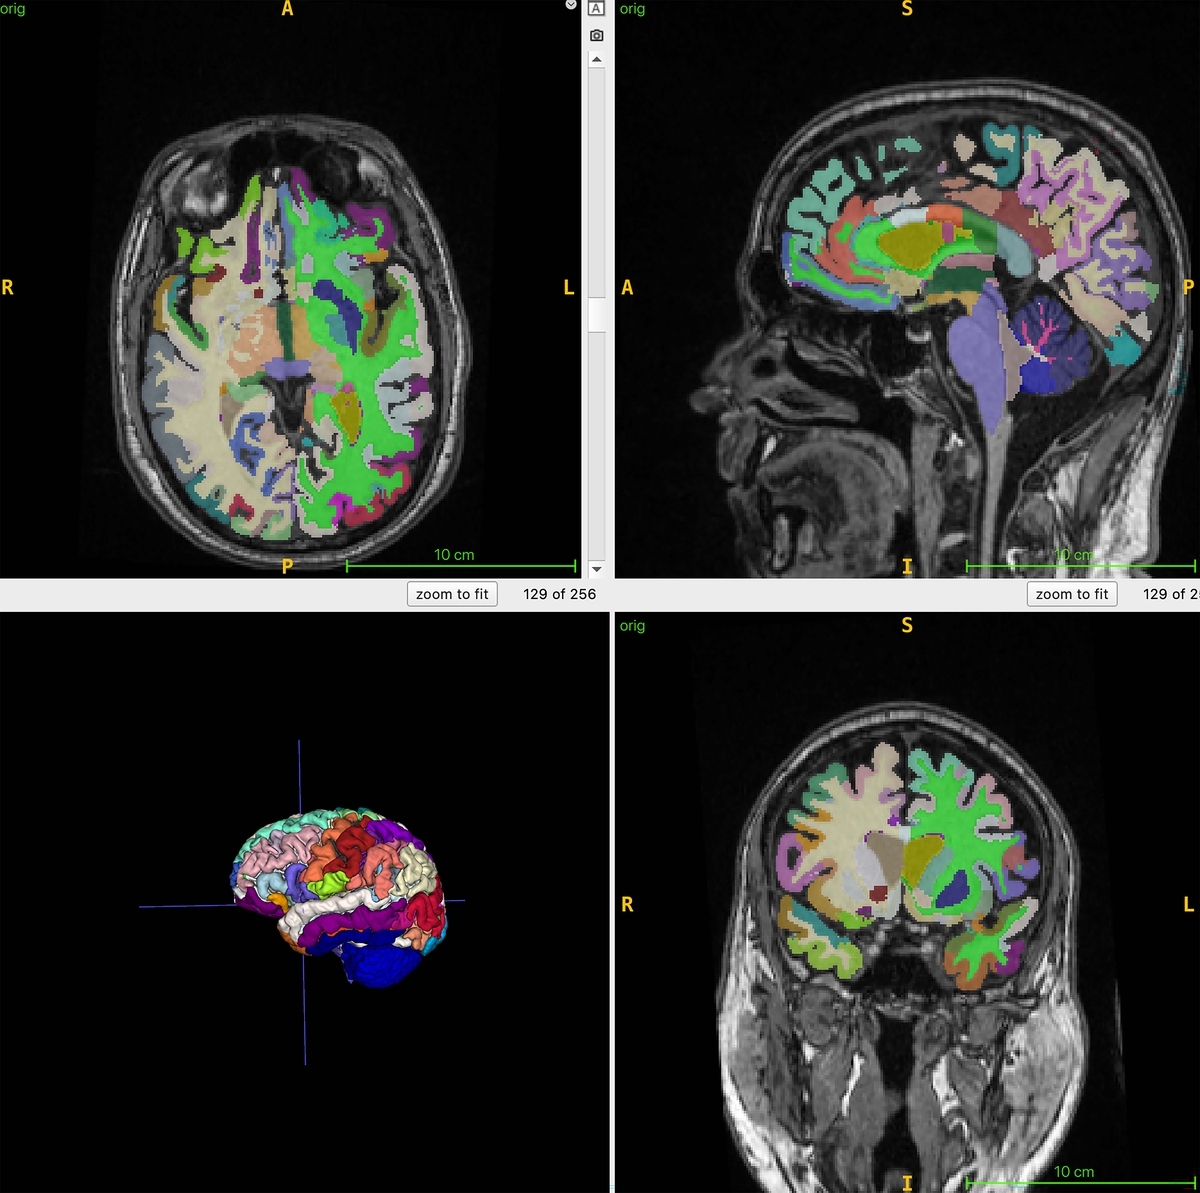

연구팀은 이 연구에서 뇌의 구조적 MRI 영상의 부위별 부피를 기반으로 추정한 뇌 나이와 전신 MRI로 측정한 총근육량과 내장지방, 피하지방 사이의 연관성을 인공지능 알고리즘으로 분석했다.

이들은 4개 지역 거주자 1천164명(평균 나이 55.17세)을 대상으로 전신 MRI를 촬영하고 이를 지방과 체액, 근육 등이 다른 색으로 보이게 하는 기법과 결합해 총근육량과 내장지방 피하지방, 뇌 나이를 정량화했다.